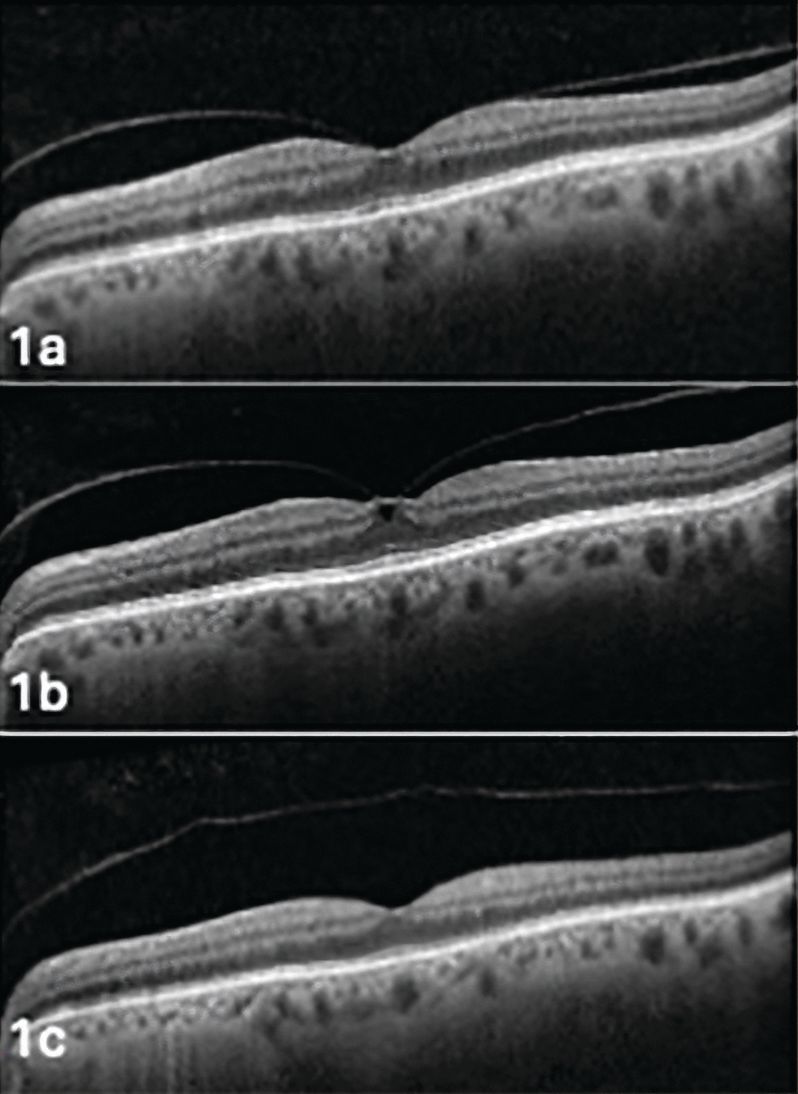

Figure 1. Evolution in the same patient of vitreomacular adhesion (Figure 1a) to vitreomacular traction (Figure 1b) to posterior vitreous detachment (Figure 1c). Image courtesy of Jim Williamson, OD, FAAO, FORS.

Because there are sites of stronger vitreoretinal adhesion, the PVD process occurs in stages (Figure 1). The vitreous first detaches in the perifoveal area, followed by release of the vitreofoveal adhesion in stage 2. Stage 3 denotes a near-complete PVD with only vitreopapillary adhesion. Detachment of this final area marks a stage 4 or complete PVD.5 Clinically, this will appear as a Weiss ring over the optic nerve or the ability to view the posterior vitreous cortex using the slit lamp (Figure 2).10 The Weiss ring, however, does not confirm that there may still be attachments in the peripheral retina.11